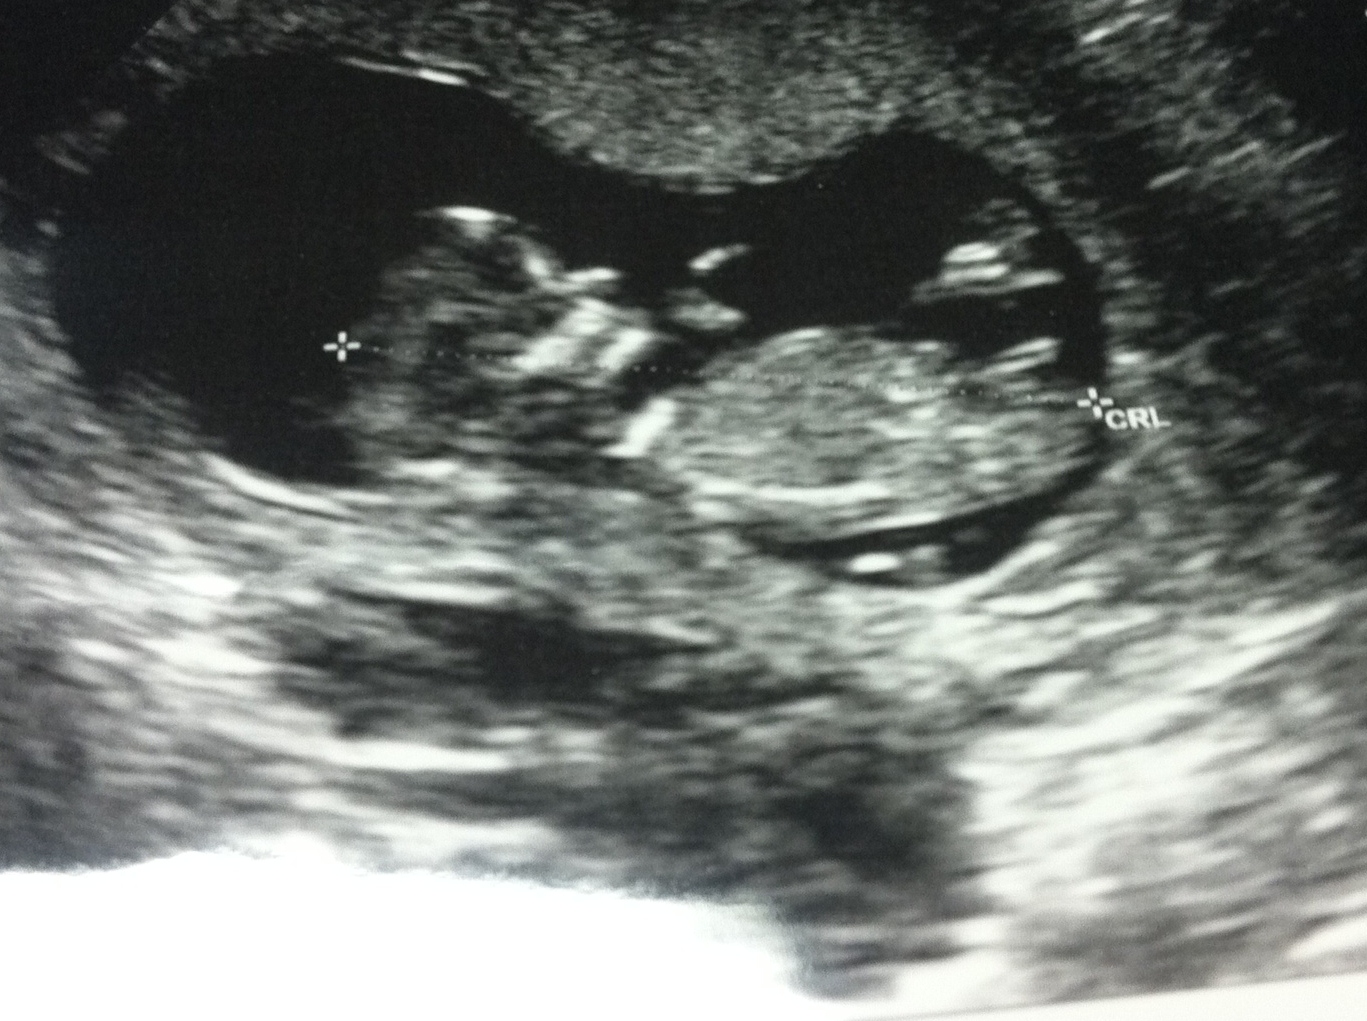

just wondering what your thoughts are on this nub. Baby is 12+1. Thanks! :cool: